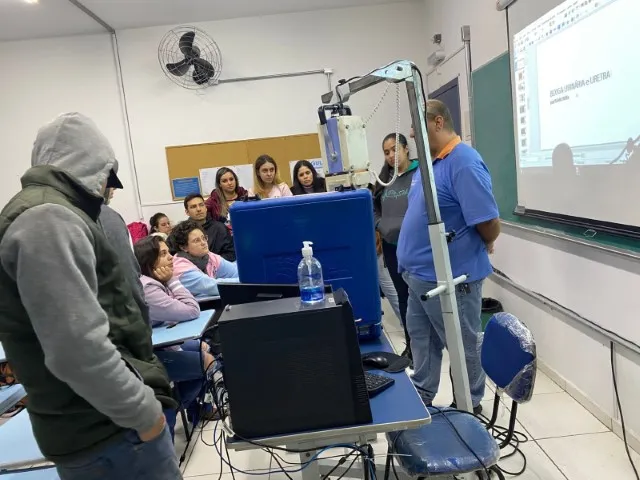

As turmas do 6º, 7º e 8º semestres de Medicina Veterinária tiveram a oportunidade de participar de uma palestra sobre Raio x em animais de pequeno porte e silvestres, com o técnico de raio X Leandro Magoga. O bate papo foi na segunda-feira, 29 de agosto, na aula do professor Erick Villela.

Leandro Magoga trabalha há mais de 6 anos como técnico de raio X de animais de pequeno porte, silvestres e exóticos, e mostrou para as turmas de Medicina Veterinária alguns pontos importantes na hora de fazer a radiografia, como o aparelho que se utiliza. Magoga ainda conversou sobre como fazer a calibragem do aparelho, a colimação (processo de alinhamento das lentes), o tempo de disparo e a quantidade de raios emitidos por diferentes aparelhos.

O professor Erick Villela quis mostrar como esse processo e aprendizado é essencial para a carreira profissional dos estudantes, já que em algumas clínicas é pedido que o veterinário clínico saiba o básico sobre imagem radiográfica e o posicionamento dos animais.